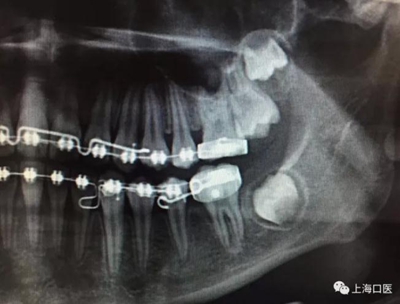

這是上海武廣增正畸工作室接診的一例非常規(guī)拔牙矯治病例,患者女性,初診年齡14歲。LL6殘冠拔除。LL7近中平移取代LL6,我們上傳了該患者一組下頜磨牙近中平移連續(xù)矯治過程的正畸X線片,與正畸界朋友分享。